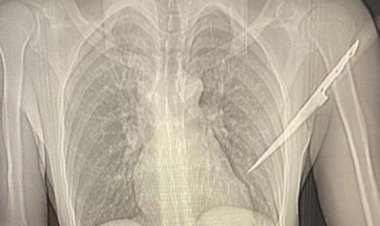

Após agressão, mulher 'crava' faca nas costas de companheiro...

O homem precisou passar por uma cirurgia para a remoção do objeto.